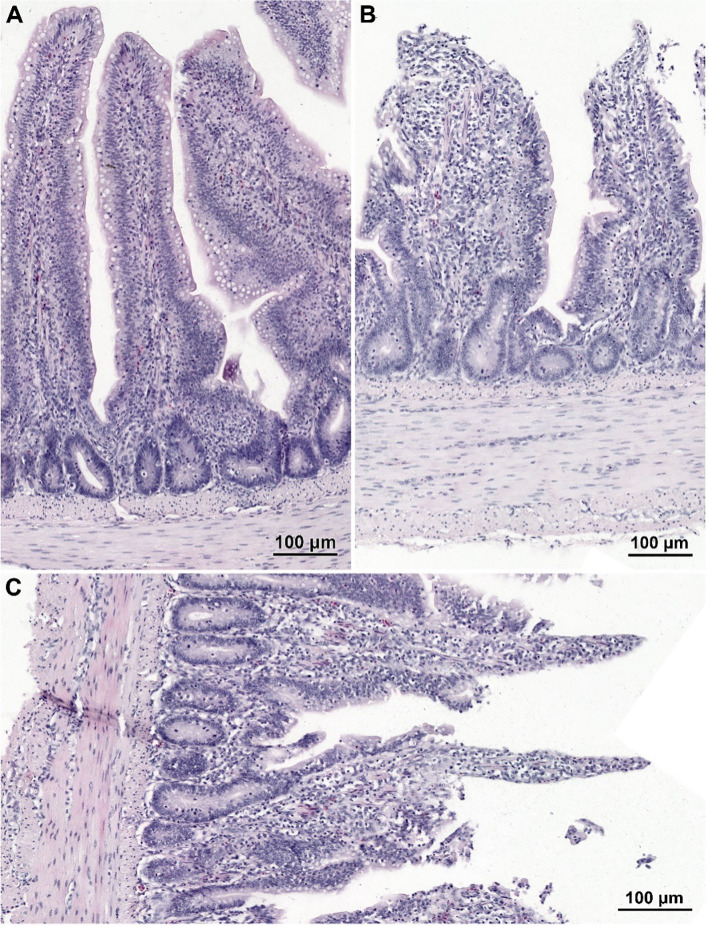

Light microscopy evaluation of histology of the small intestine

The histological structure of the small intestine in control chickens was typical of the species. Well-developed villi were observed, with the longest found in the duodenum and the shortest in the ileum, accompanied by short intestinal glands. The pathological alternations were not detected. No qualitative differences in villi structure were noted between infected groups treated with CBD, CBD + nano-Se, nano-Se, and those not supplemented with these compounds. The structure of the small intestine in animals receiving CBD + nano-Se was similar to that in the control group (f3). The villi were covered by a continuous layer of columnar cells comprising absorptive enterocytes and goblet cells. In contrast, all groups of birds infected with C. perfringens frequently exhibited areas of mucosa devoid of epithelial covering, primarily on the apical portions of villi (f3, f4). However, the shedding of enterocytes from lateral portions of the villi was also noted (f4). Occasionally, the loss of epithelial cells coincided with shortened villi (f3) or villi deformation (f3). Some villi displayed connective tissue stroma infiltrated by inflammatory cells (f4) and, in certain cases, an increased presence of smooth muscle cells (f4). Although the intestinal glands were not affected by the C. perfringens infection, mitotic figures appeared to be more numerous in infected chickens than in non-infected birds, except for the infected group treated with CBD + nano-Se.

Light and electron microscopy analyses were performed to assess the histological structure and ultrastructure of the intestine. These studies showed that CBD + nano-Se supplementation is safe for the gut and does not cause negative qualitative changes in the histological structure of the small intestine and the ultrastructure of the jejunum. This result is partly consistent with a study by Gangadoo et al. (ref. 54), who showed in a histopathological analysis that nano-selenium did not cause harmful effects, revealing intact epithelial cells in the gastrointestinal tract in broiler chickens. This result also confirms the current authors’ previous study (ref. 32), which found that the combination of these two nutritional additives showed no opposite effect on mediating the host response to infection. This confirms that understanding the mechanisms of action of cannabidiol and nano-selenium is of great interest in developing new possibilities for promoting intestinal barrier function. In the present experiment, C. perfringens infection did not cause necrotic enteritis. The changes were moderate in character and mainly involved damage to the intestinal epithelium. This correlates with the clinical condition of the chickens, as none of the challenge tests induced overt clinical signs of NE. According to Timbermont et al. (ref. 16), NE is characterized by a strong inflammatory response in its early stages, where the most significant early changes are seen at the interface between the enterocyte domain and the lamina propria. An ultrastructural study by Olkowski et al. (ref. 55) shows that primary modifications occur at the level of basal and lateral domains of the enterocytes. In contrast, the apical domain of enterocytes remains intact even in the face of advanced necrotic changes. This indicates that mucosal necrosis does not result from direct damage to the mucosal epithelium. Rather, the necrotic death of enterocytes is a consequential effect of destroying lamina propria, the extra-cellular matrix, and intercellular junctions. This result is consistent with the study of Olkowski et al. (ref. 56), who also found no overt mucosal necrosis typical of NE field cases in a histological examination in C. perfringens-infected chickens. This is very important because the current study aimed to induce a moderate infection, mimicking a subclinical infection rather than the acute form. It should be mentioned here that increased collagenolytic enzyme activity in the mucosal and intestinal tissue environment is an integral component of the pathological process leading to NE (ref. 32, ref. 55). However, none of the supplements administered had a remarkable effect on the morphological changes in the gut developed during infection. Perhaps it was too short a time to see changes at the microscopic level because, at the molecular level, treatment with nano-Se and CBD significantly increased the mRNA expression of genes such as junctional adhesion molecule 2 and zonula occludens-1, which are responsible for intestinal integrity (ref. 32, ref. 33). In addition, in a previous study, the authors also showed that cannabidiol and nano-selenium in C. perfringens-infected chickens promoted changes in the extracellular activity of bacterial enzymes in the gut, which may indicate increased energy consumption under induced stress conditions (ref. 32).